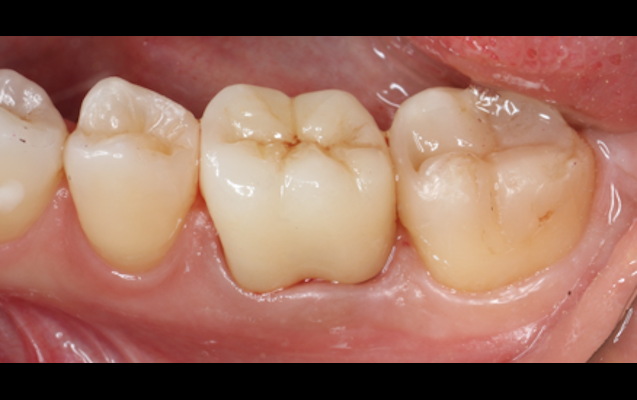

| 治療名 | 臼歯ダイレクトボンディング |

| 基礎データ | 54歳/女性 |

| 治療期間 | 1回 |

| 執刀医 | Dr. 大杉 |

| 治療費 |

6万円 ■内訳 精密コンポジットレジン修復3万×2本 |

| 概要 |

銀歯の見た目が気になる、銀歯の下のむし歯が気になるとのことで、見た目を改善する治療をさせていただきました。歯にしっかりと接着するので適合も良く、清掃性も高いです。 |

| 主な副作用 |

コンポジットレジン破損 |